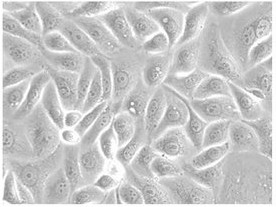

Morphology: epitheloid cells growing in monolayers

Fig. 1. EFE-184 cell (Wang B, Shao W, et al., 2020).